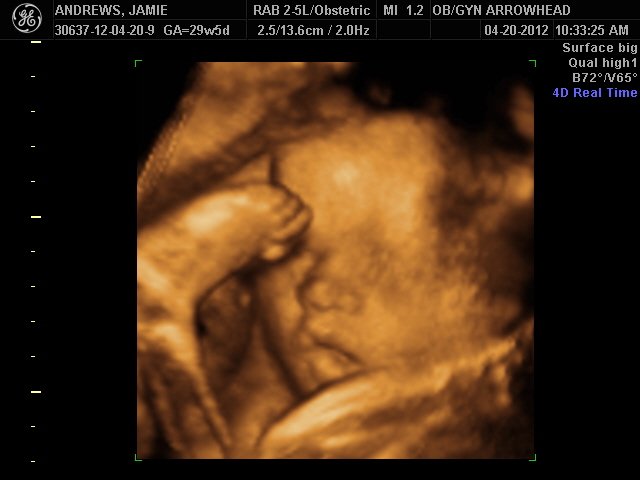

We offer complimentary 3D/4D Ultrasounds to all our OB patients around 30 weeks! The following photos are some examples of our work, shown with permission from our patients.